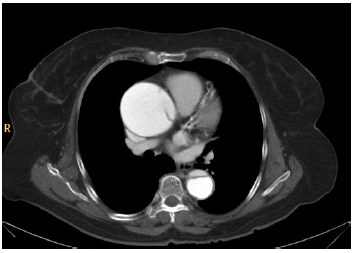

Analise a imagem a seguir.

A análise da imagem de tomografia computadorizada acima sugere que

o meio de contraste opacificou a luz verdadeira da dissecção aórtica.